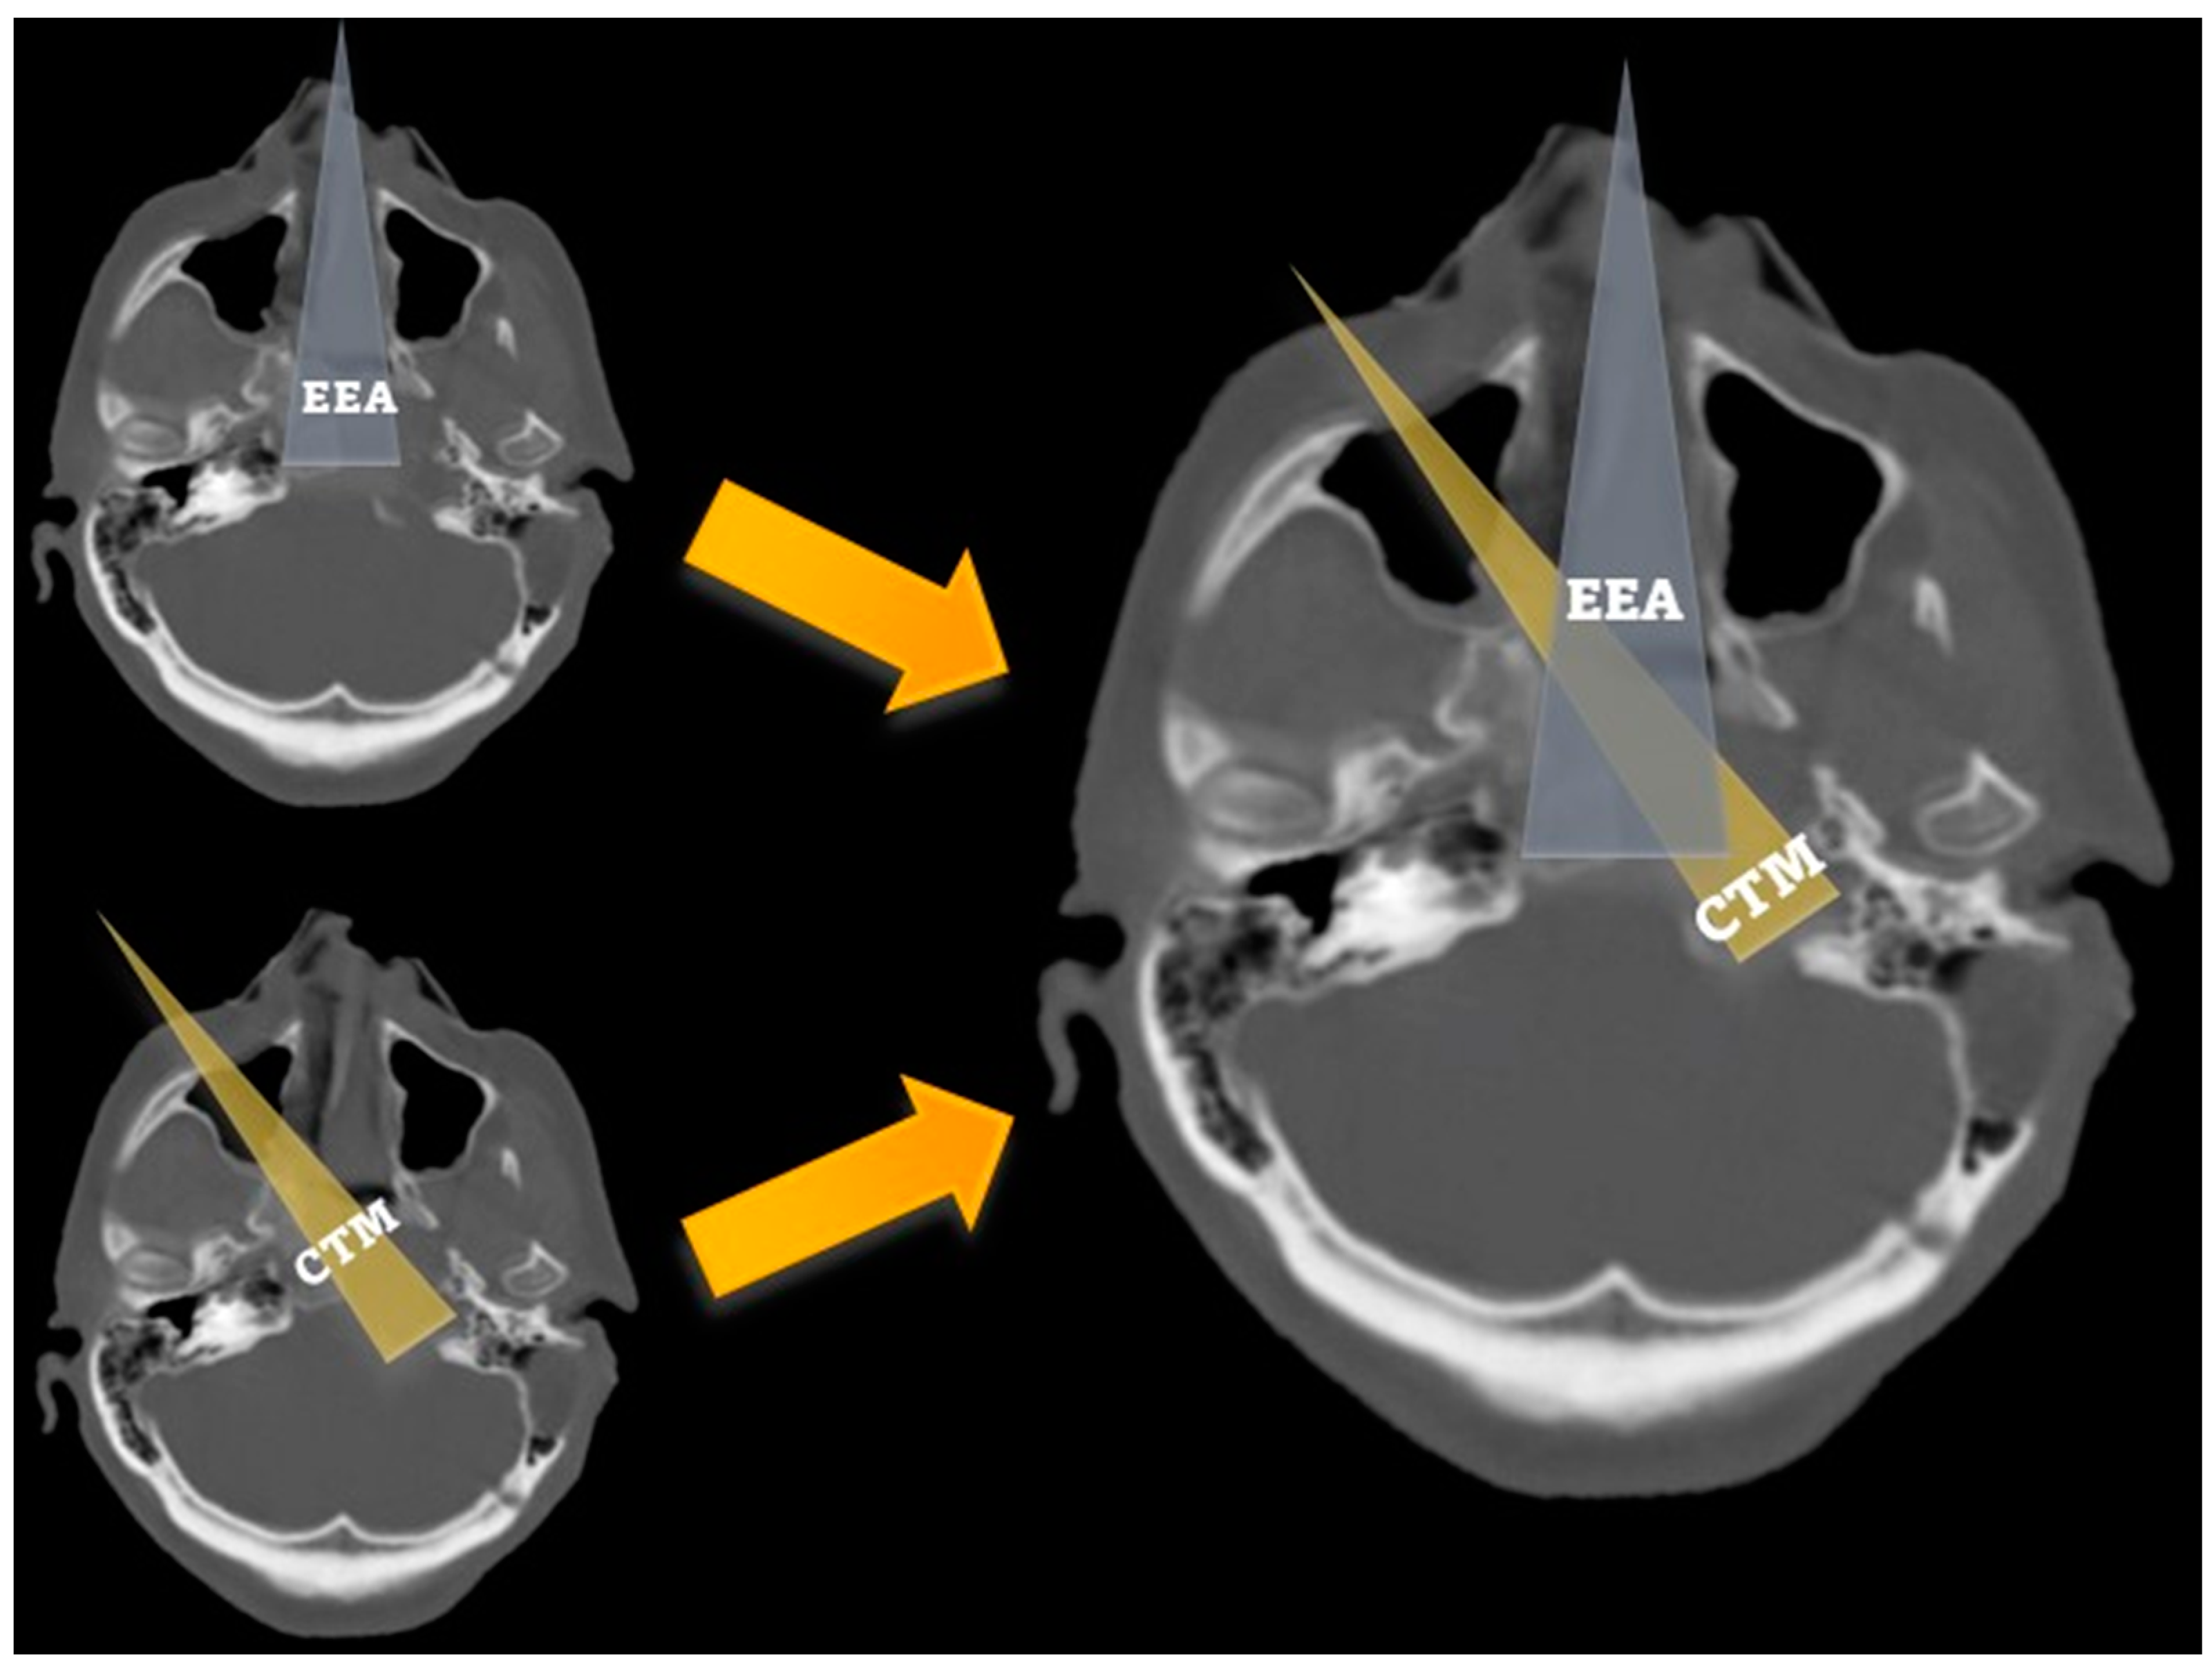

2.3. Quantitative Analysis and Surgical Operability

3.1. Anthropometric Measurements and Surgical Operability

| Angle of attack (°) | 161.1 (8.6) | 140.6 (5.7) | 0.001 |

| Surgical field depth (mm) | 74.3 (4.0) | 88.0 (5.8) | 0.001 |

| Petrous drilling depth (mm) | 17.2 (4.0) | 11.0 (3.3) | 0.008 |